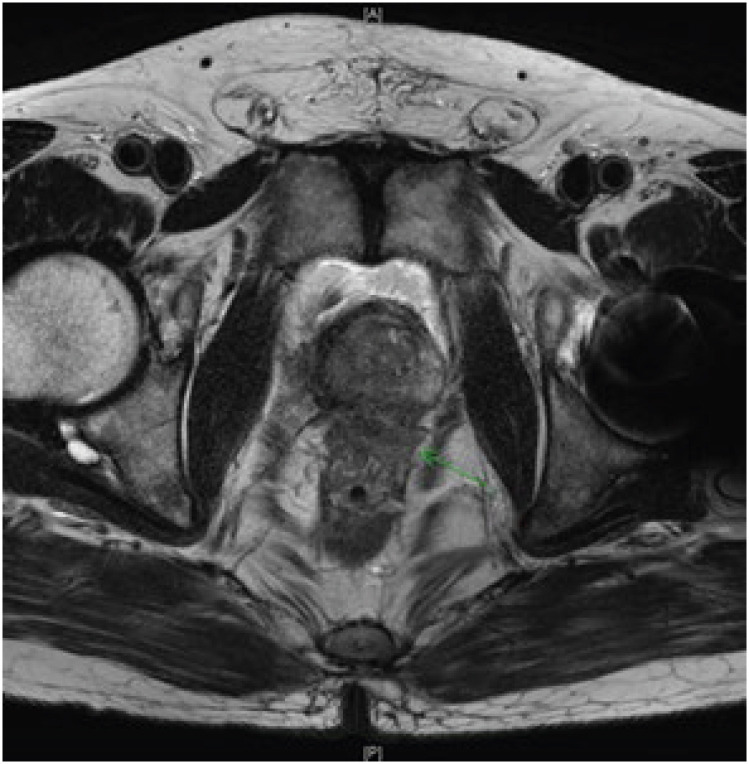

Case presentation: Patient A: A 61-year-old man worked as a city bus driver for approximately 17 years, from 2002 to 2019, and was exposed to night-shift work during this period. In March 2017, the patient was diagnosed with high-grade prostate cancer through core-needle biopsy after experiencing stinging pain lasting for 2 months. Patient B: A 56-year-old man worked as an electrician and an automated equipment operator in a cement manufacturing plant for 35 years from 1976 to 2013 and was exposed to night-shift work during this period. In 2013, the patient was diagnosed with high-grade prostate cancer through core needle biopsy at a university hospital because of dysuria that lasted for 6 months.

Abstract Image